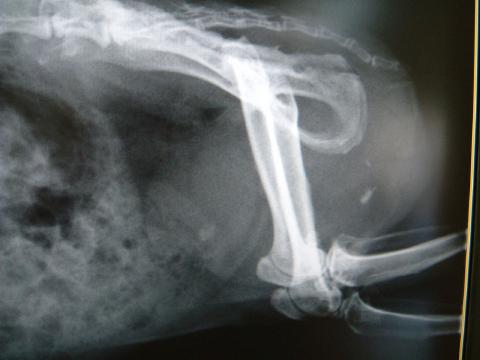

レントゲン検査で尿道内の小さな結石陰影を確認。

再度のレントゲン検査と皮膚にフケが見られたので、皮膚の鱗屑のスタンプ検査を実施した。

レントゲン検査において、尿道部と思われる位置に砲弾状の不整形陰影があり、この所見は1ヶ月前にも認められ、その時点よりも拡大していました。

また、膀胱内と思われる位置にもやや不鮮明な不整形陰影が確認されました。

診断:尿道結石 膀胱結石?